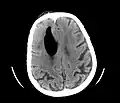

Pneumocephaly

Pneumocephalus is the presence of air or gas within the cranial cavity. It is usually associated with disruption of the skull: after head and facial trauma, tumors of the skull base, after neurosurgery or otorhinolaryngology, and rarely, spontaneously. Pneumocephalus can occur in scuba diving, but is very rare in this context.